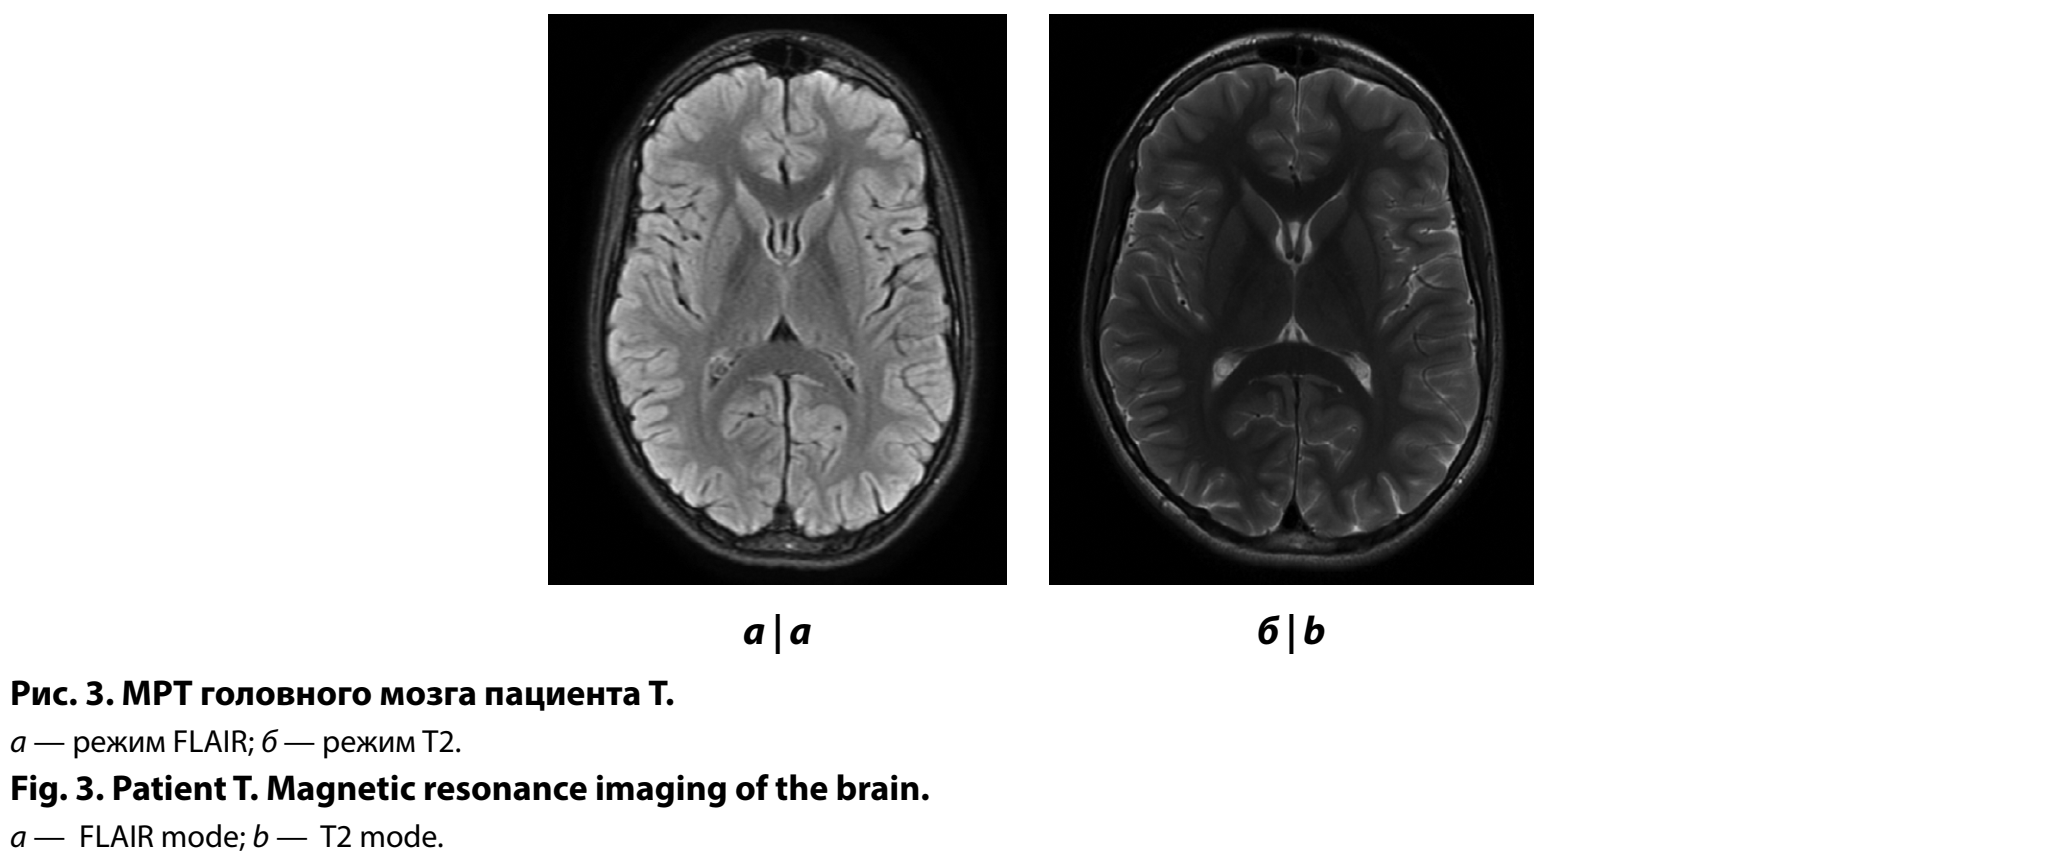

С целью оценки структур головного мозга проведено МРТ головного мозга — данных за объёмное/очаговое поражение вещества головного мозга не получено (рис. 3).